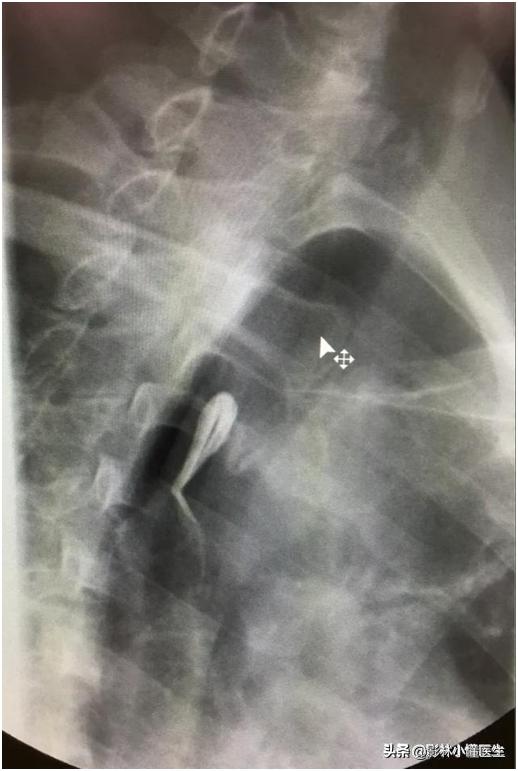

棉絮挂在食道

挂棉征

(X线检查先拍一张平片,如果能看到明显的异物,无需进行吞钡检查已明确诊断);如果平片没有看到明显高密度异物,需要吞服少量棉絮,然后服钡,当有异物时会出现挂棉征,如上图)。但要提醒的是,对于较大异物,特别是尖锐异物已伴发炎症甚至穿孔者,则应慎用或禁用絮钡检查为妥。